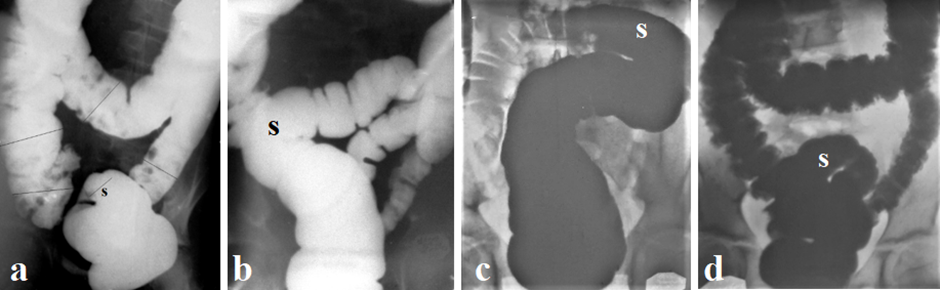

Figure 3. Two methods for determining the width of the rectum.

a) Measurement of the maximum width of the rectum on a lateral radiograph of a 14-year-old patient. Knowing the true diameter of the radiopaque marker located near the anus (1.6 cm), we calculated the true diameter of the rectum (4.5 cm). The age norm is 3.6–4.6 (3.95±0.07 cm).

b) Radiograph from the article by Koppen et al. [35].

c) In the copy of (b), I have shown that in the frontal projection there is a combination of shadows of two branches of the rectum. A sharp expansion of all parts of the colon is due to a decrease in tone caused by the disease (intussusception) and distension of the intestine under high pressure.

d) The lateral radiograph shows a wide fecal stone in the rectum. The peristaltic wave (arrow) strives to expel the stone through the anal canal, but since the width of the anal canal cannot pass feces of this size, the fecal stone stretches the muscles of the pelvic floor. This leads to stretching of the PRM. Shortening of the anal canal (yellow line represents the length of the functioning part of the anal canal; red line is normal anal canal length) is evidence of descending perineum syndrome.

Thus, because of methodological errors, the authors obtained a result that contradicts common sense, since the width of the rectum in children under 6 years of age cannot in principle be the same as in adults. This false result led to another false result. In the study by Koppen et al [35], the dilated rectum in children with intractable functional constipation was assessed as normal in size, which led to a false statement about the possibility of segmental colonic dilation. Such disregard for common sense can only be explained by the fact that Koppen IJN in both cases received grants for advertising high resolution manometry. As a result, a supposedly scientific justification was proposed for resection of the dilated segment, which, as shown above, not only does not relieve children of the disease, but does not help to reduce the number of laxatives [33].